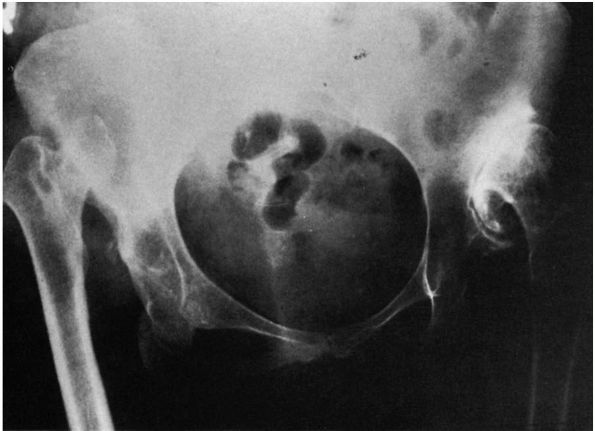

institute treatment so that normal development may occur. If the hip

remains completely dislocated, its natural history depends on two

factors: the presence or absence of a false acetabulum and

bilateralness.

complete dislocations do well, maintaining a good range of motion and

little functional disability. Completely dislocated hips with

well-developed false acetabuli, however, are more likely to develop

degenerative joint disease in the false acetabulum and have a poor

clinical result (Figure 15-6). Degenerative

joint disease in the false acetabulum usually occurs in the fourth and

fifth decades of life. In bilateral complete dislocations, lower-back

pain may occur. This may be secondary to the hyperlordosis of the

lumbar spine associated with the hip flexion adduction deformities

caused by the dislocations.

is affected by the secondary problems of limb length inequality,

ipsilateral knee deformity, pain (usually on the lateral side of the

knee), secondary scoliosis, and gait disturbances. In these patients,

the same factors concerning the development of secondary degenerative

changes in any false acetabulum that may occur are also applicable.

![]() |

|

FIGURE 15-6.

Radiograph of a 43-year-old woman with complete dislocation of both hips. She has no symptoms on the right but has disabling symptoms from the left hip. She has no false acetabulum on the right but has a well-developed false acetabulum on the left with secondary degenerative changes present. (Weinstein SL. Natural history of congenital hip dislocation [DDH] and hip dysplasia. Clin Orthop 1987;225:62-76) |